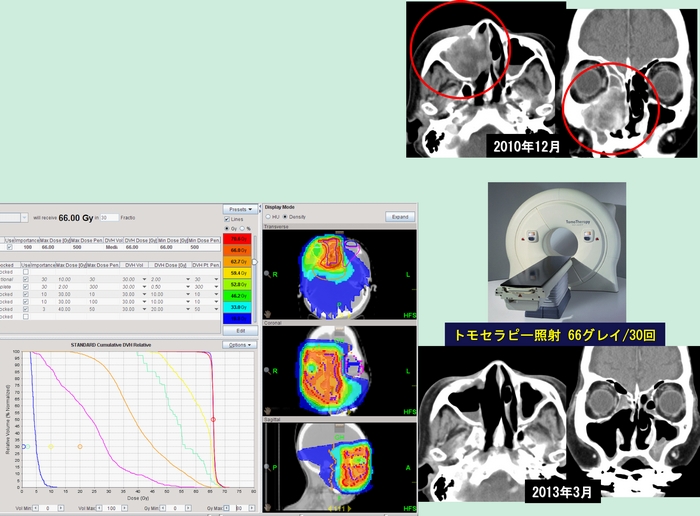

中咽頭がん扁平上皮がんサバイバー三枝幹弥さんへのインタビューです 厳しいガン体験が教えてくれたこと仕事家族東京マラソン 基本情報 名前 三枝幹弥さん 年代性別 40代男性 病名 中咽頭がん扁平上皮癌 進行ステージ ステージⅳa 治療期間 2010年11月.

中咽頭癌 扁平上皮癌 Stage 放射線 サイバーナイフ 後の残存腫瘍の治療

放射線治療 頭頸部がん 九州大学病院のがん診療 九州大学病院 がん

がん診療 放射線治療科 横浜市立大学附属 市民総合医療センター